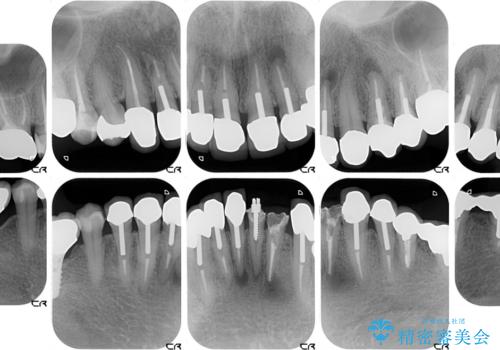

- 下顎の前歯に激痛を覚えて来院された患者様です。

取り急ぎ下顎前歯数歯の根管治療を、銀座しらゆり歯科医院長の林先生にお願いし、それ以外に気になっている、不自然な色調のクラウン、金属部分が見えてブラッシングがしにくいインプラント補綴、口元の突出感、出血のしやすい歯周ポケットなど、全てを解決するための治療を行うこととしました。